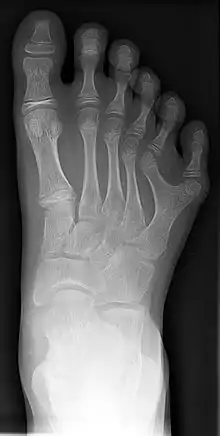

Кістки стопи людини включають 26 кісток і утворюють три відділи:

- Заплесно (лат. tarsus) — 7 кісток проксимального відділу стопи, які з'єднуються з кістками плесна.

- Плесно (лат. metatarsale) — 5 коротких трубчастих кісток стопи, розташованих між заплесном і фалангами пальців.

- Фаланги (лат. phalanx) — 14 коротких трубчастих кісток, що складають сегменти пальців стопи. Дві фаланги утворюють великий палець, інші пальці складаються з трьох фаланг.

Усього в тілі людини нараховується 206 кісток, 52 кістки розташовуються в стопах, що становить четверту частину від усіх кісток тіла.